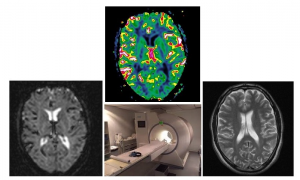

Πάνου Θεοδώρα, Επιστημονικός Υπεύθυνος του ερευνητικού έργου με τίτλο: «Γνωστικοί, Ψυχοσυναισθηματικοί και Νευροαπεικονιστικοί Προγνωστικοί Δείκτες Εξέλιξης της Σκλήρυνσης κατά Πλάκας κατά τα αρχικά στάδια»

H διαχρονική μελέτη στοχεύει στη διερεύνηση γνωστικών, ψυχοσυναισθηματικών, και νευροαπεικονιστικών παραμέτρων κατά τα πρώιμα στάδια της Σκλήρυνσης κατά Πλάκας (ΣκΠ) που σχετίζονται με την μακροχρόνια έκβαση της νόσου. Η μελέτη λαμβάνει υπόψη εκτενή νευροαπεικονιστικά, νευρολογικά και νευροψυχιατρικά δεδομένα που καταγράφηκαν στην περίοδο 2013-4 κατά την αρχική κλινική αξιολόγηση 80 ασθενών με ήπιας βαρύτητας ΣκΠ και προβλέπει τη νευρολογική και νευροψυχιατρική επαναξιολόγηση των ίδιων ασθενών με ταυτόσημες διαδικασίες μετά από παρέλευση 5 ετών (κατά τα έτη 2018-9). Ο σχεδιασμός της μελέτης επιτρέπει τον έλεγχο σύνθετων σχέσεων μεταξύ σημείων νευροπαθολογίας, που δεν είναι ανιχνεύσιμα με συμβατικές τεχνικές μαγνητικής τομογραφίας, γνωστικών μεταβλητών (πχ., μνήμη επεισοδίων, νοητική ευελιξία, ταχύτητα επεξεργασίας, μνήμη εργασίας), καθώς και δεικτών της συναισθηματικής κατάστασης των ασθενών (αγχώδη και καταθλιπτική συμπτωματολογία), με τη μορφή διαμεσολαβητικών ή ρυθμιστικών επιδράσεων